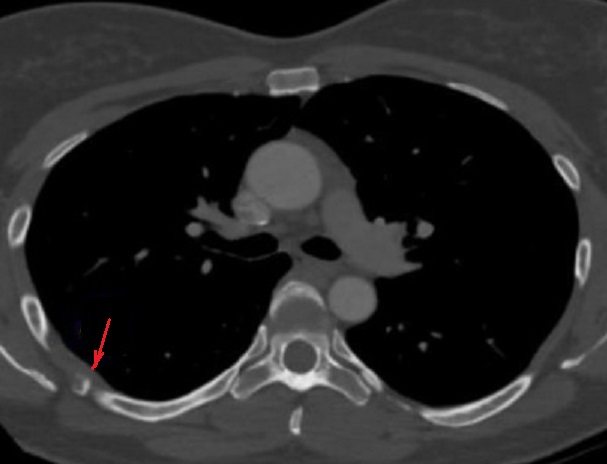

Aspect radiologique TDM de

nodule calcification parietale (flèche rouge )

d'une myosite ossifiance chronique de muscle

intercostale posterieure droit . Image radiologique

TDM en coupe axiale |